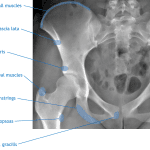

Findings

- Acute nondisplaced fractures of the right superior and inferior pubic rami

- Acute nondisplaced fracture of the right pubic body with extension into the pubic symphysis

- Inferiorly distracted avulsion fracture from the medial aspect of the right ischial tuberosity

- Partially imaged cephalomedullary nail fixation of a remote right intertrochanteric femoral fracture with a superioly displaced lesser trochanteric fragment and surrounding heterotopic ossification

- Mild degenerative changes of the hips and sacroiliac joints

- Partially imaged advanced degenerative changes of the lower lumbar spine

- Osteopenia

- Vascular calcifications